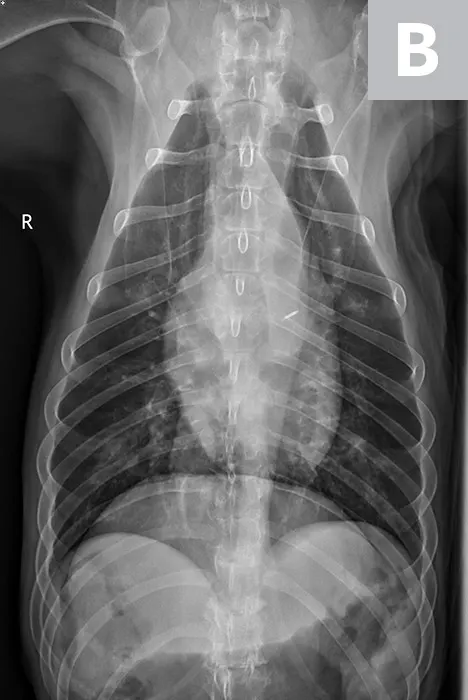

Serum chemistry profile and CBC results were normal, and heartworm antigen test results were negative. Thoracic radiography (right lateral, left lateral, ventrodorsal) revealed a diffuse bronchial pattern but was otherwise unremarkable with no cardiomegaly (vertebral left atrial size, 2.1 [normal, 1.4-2.2]; vertebral heart scale, 9 [normal, 8.7-10.7]) or observable airway collapse (Figure 1). Arterial blood gas showed partial pressure of arterial oxygen 97 mm Hg (normal, 81-103 mm Hg). Echocardiography revealed myxomatous mitral valve degeneration (B1) with no evidence of pulmonary hypertension.2 Laryngoscopy/bronchoscopy showed moderate mucosal irregularity and increased mucus of the lobar bronchi (Figure 2) with normal laryngeal function. Concurrent dynamic bronchial collapse of the left and right mainstem bronchi (grade II/III) was observed (Figure 3).3 Bronchoalveolar lavage was performed and submitted for cytologic evaluation and aerobic culture. Cytology revealed nonseptic neutrophilic inflammation (Figure 4); aerobic culture was negative.